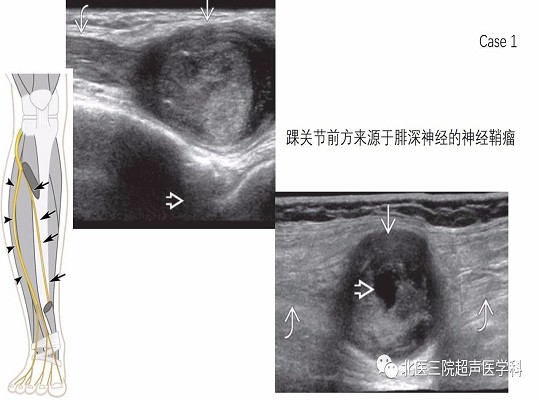

【经典超声书籍解读】周围神经肿瘤性病变(上)